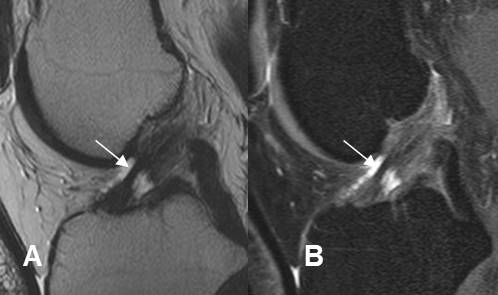

Fig 165. Esguince GII.

A: RM sagital en T2 y B: RM sagital en STIR. Adelgazamiento, con solución de continuidad en la mayoría de las fibras del LCA, por ruptura parcial.